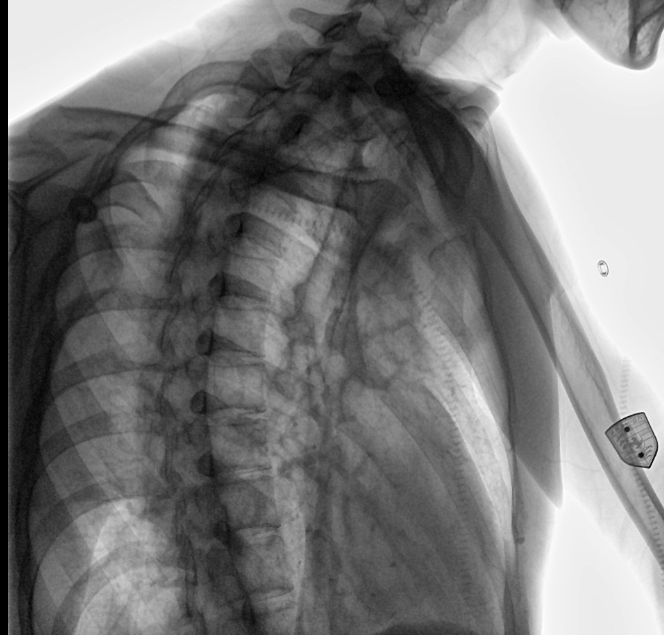

安健科技動態(tài)平板DR-DTP571

位于衡水市中醫(yī)醫(yī)院的動態(tài)平板數(shù)字化X射線系統(tǒng)DTP571具備高速高清點片功能。這是一款對放射科十分友好的產(chǎn)品。因為它把高速和高清點片結(jié)合,既能方便影像技師有效地抓拍需要的病灶的影像,又能給予影像醫(yī)生清晰的影像進(jìn)行診斷。

動態(tài)觀察診斷,實時高清點片